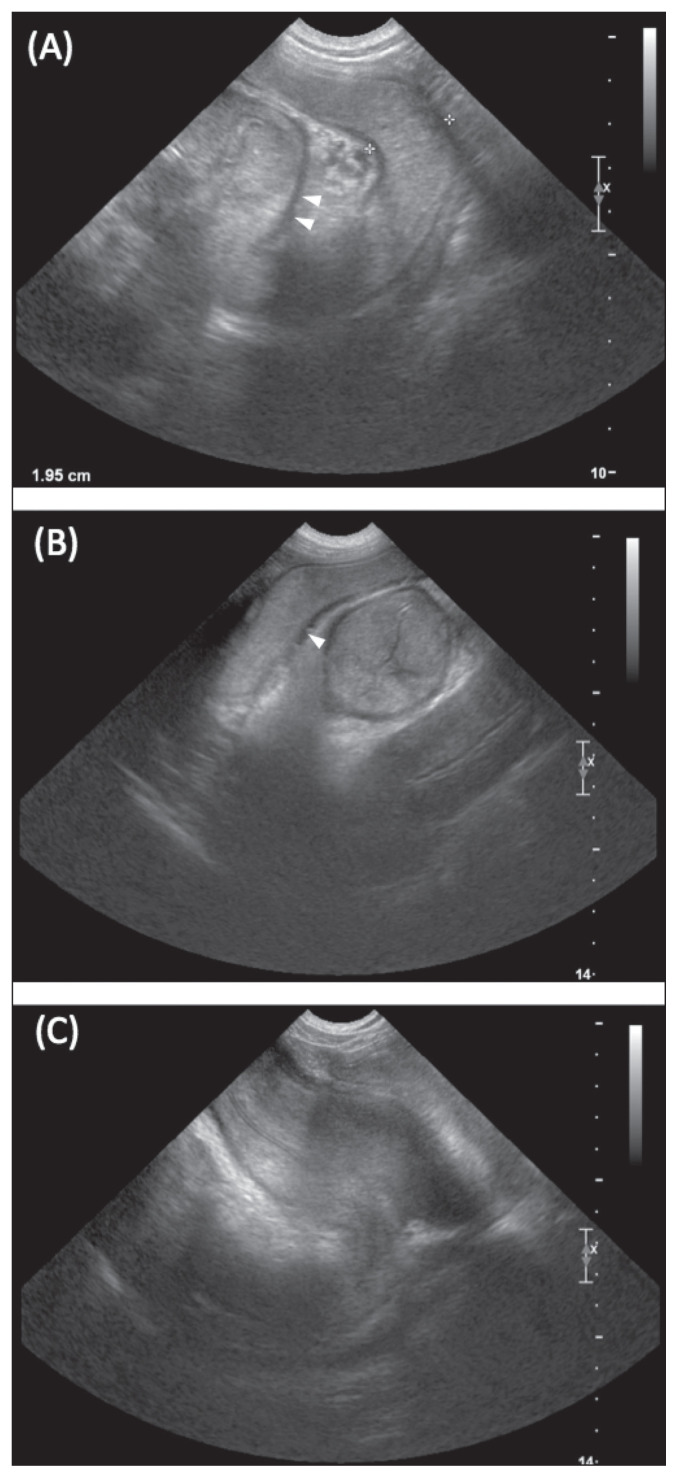

Figure 2. Transverse ultrasound view showing the pathognomonic target sign (also called bull's eye sign or doughnut sign) of intussusception, demonstrating concentric alternating hyperechoic and hypoechoic rings representing the layers of invaginated bowel.

| Target Sign (Transverse) | Multiple (greater than 5) concentric alternating hyperechoic and hypoechoic rings; PATHOGNOMONIC for intussusception |

| Multiple Parallel Lines (Longitudinal) | Alternating hyperechoic and hypoechoic linear streaks; "sandwich sign" |

| Pseudokidney Sign | Seen when intussusception is curved and mesentery visible on one side; resembles kidney shape |

| Hyperechoic Crescent | Invaginated mesentery appears as hyperechoic semilunar structure; may see congested vessels within |

| Associated Findings | Proximal bowel dilation, fluid accumulation, hyperperistalsis (acute) or absence of peristalsis (chronic), peritoneal effusion |

Board Tip - Memory Aid: "TARGET your diagnosis with ultrasound!" The TARGET SIGN is pathognomonic for intussusception. Think of it like looking at a dartboard (target) from above - you see concentric rings. On longitudinal view, you see "stacked pancakes" or parallel lines.

Figure 2 - Ultrasound triple circle/target sign (transverse and longitudinal views, double intussusception, Case 1): Aprea F et al. (2012). "Ultrasonographic diagnosis and surgical management of double intestinal intussusception in 3 dogs." Can Vet J. Figure 2. PMC3398523. URL: https://pmc.ncbi.nlm.nih.gov/articles/PMC3398523/ - Open Access.